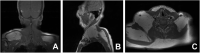

Case presentation: A 59-year-old Korean female came in with a chief complaint of palpable mass present in shoulder and upper back regions. Images showed diffuse non-encapsulated adipose tissue in the subcutaneous layer of the suboccipital, posterior neck area. The patient wanted to remove the mass for cosmetic reasons and discomfort. Excisional biopsy was planned. Preoperative blood analyses showed deteriorated liver function, and the computed tomography findings were consistent with liver cirrhosis. Detailed history taking revealed that she consumed highly levels of alcohol. Lipectomy was performed and the histological findings demonstrated large dystrophic adipocyte morphology. The patient was recovered uneventfully.